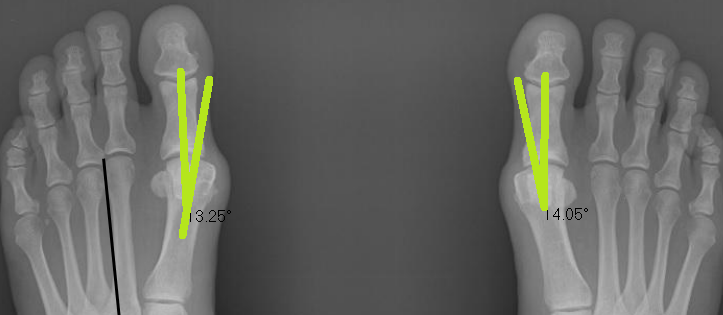

Below is a patient who has completed a short course of Foot Mobilisation Therapy here at Corrective Foot Solutions.Before the treatment the bunion angles are 21.22 and 24.74 degrees. Normal angles are between 12-15 degrees.

Post treatment angles are 14.8 and 13.3 degrees- a significant change of 11 and 7 degrees. NO surgery required and a happy patient!